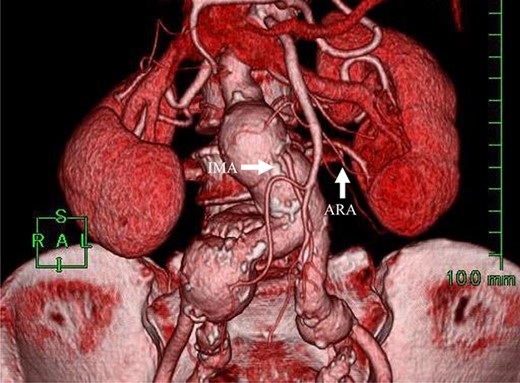

Angiography for decision-making revealed a type II endoleak from the IMA to the AAA, but no other visible endoleak (Fig. 2). Based on these findings, we planned additional EVAR for left CIAA, which was thought to have enlarged in natural course, and IMA embolization for the type II endoleak associated with sac enlargement. A staged strategy was devised. IMA embolization was planned several days after EVAR. Sac angiography from the IMA via Riolan’s arcade showed a flow-through endoleak to the ARA as a drainage artery (Fig. 3). Based on this finding, we embolized the ARA and the IMA with coils via Riolan’s arcade (Fig. 4). Selection and embolization of the drainage artery were technically feasible because of the flow from the IMA to the ARA. No deterioration of renal function due to ARA embolization was observed. One year after treatment, a CT scan demonstrated that the sac shrank to 42 mm with no evidence of a continuing endoleak (Fig. 5).

Coil embolization of the IMA and ARA was performed successfully via Riolan’s arcade.

In this case, the IMA and ARA branched closely from the sac, and their diameters were both large (IMA 3.7 mm, ARA 2.6 mm). We thought that continued flow from the IMA to the ARA via the sac led to sac enlargement. Embolization was successfully performed, and after treatment the sac shrank. No complications, such as renal deterioration, were observed.